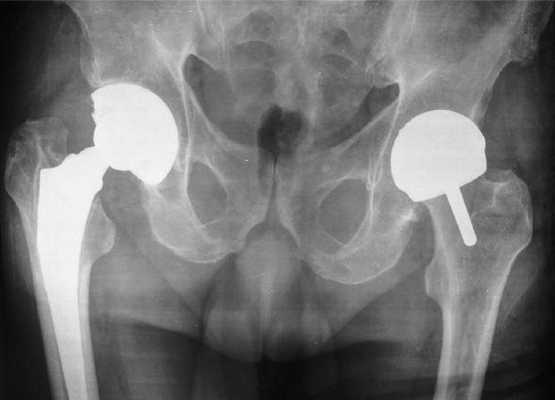

- Частичная артропластика. В процессе хирургии на имплант меняется головка и фрагмент шейки бедренной кости, вертлужная впадина остается нетронутой. Искусственная головка при движениях будет находиться в тесной взаимосвязи с естественной суставной поверхностью тазового углубления. Этот способ еще называют однополюсным протезированием. Он назначается только при одностороннем поражении сочленения (в области бедренной кости). Часто используется при нарушении целостности шейки бедра и остеонекрозе головки, если хрящевые покровы вертлужного ложа в хорошем состоянии. Недостаток неполной пластики – необходимость частой замены вживленного имплантата, в среднем каждые 7 лет. . Артропластику в данном случае осуществляют на бедренной и тазовой кости одновременно. Весь сустав полностью резецируется, а затем производится возмещение всех удаленных участков элементами тотального (полноценного) протеза. Полная артропластика рекомендована при обширной дегенерации, которая разрушила, деформировала и вывела из строя весь суставной аппарат. Методика признана лучшей, так как дает самые продуктивные результаты в восстановлении полноты движений. Кроме того, тотальные конструкции обладают наивысшим запасом прочности и долговечности, срок эксплуатации – 15-30 лет.

Тотальная и поверхностная операция на рентгене.